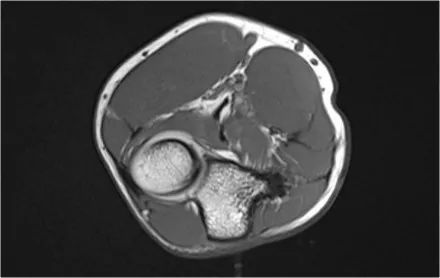

外翻过度综合征的关节病由于外翻过载,在肱骨-尺骨关节的后内侧部分存在剪切力。注意在T1W图像上看到的软骨下硬化(红色箭头)。在T2W图像上存在软骨下骨髓水肿和软骨损失(黄色箭头)。

下图是20岁棒球投手的图像。

冠状图像上有一个美丽的UCL前束,但注意到关节内侧部分有骨赘形成(红色箭头)。当我们按照顺序向下看,可以看到存在一小部分低信号强度(黄色箭头),这是UCL的一部分撕裂。